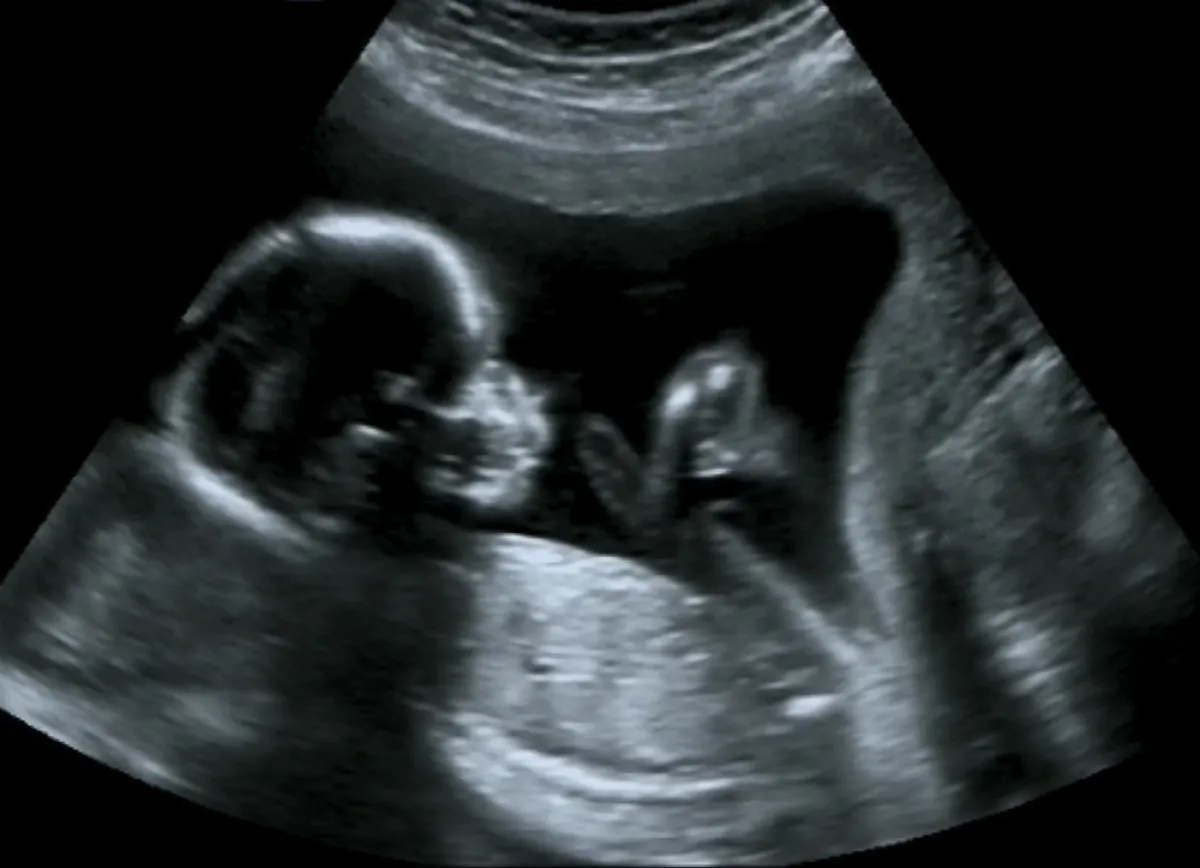

في هذا الشهر تدخل الحامل مرحلة مميزة؛ فمع بداية الأسبوع الرابع عشر يصبح الجنين أكثر حيوية ونشاطاً، فإلى جانب حركات أطرافه غير الإرادية، فهو يستطيع فتح فمه وتحريك عينيه وتقطيب حاجبيه، وسوف تشعرين بطفلك يتحرك لأول مرة قرابة الأسبوع السادس أو السابع عشر وعلى نحو مفاجئ، لكن هناك مشاكل أيضاً؛ حيث تستعيدين شهيتك وتزداد شراهتك، سيرتفع ضغط دمك، وتصابين بالزلال، وأحياناً تكونين عرضة للإجهاض.. للتحذير معنا الدكتور عبد الحميد السبيلي أستاذ أمراض النساء والتوليد.